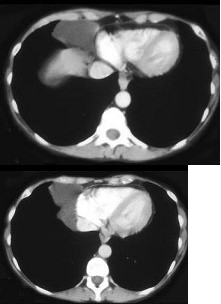

1、单项选择题  患者最近诊断有肾细胞癌,最可能的诊断是()

男婴,11月,咳嗽,结合图像,最可能的诊断是()